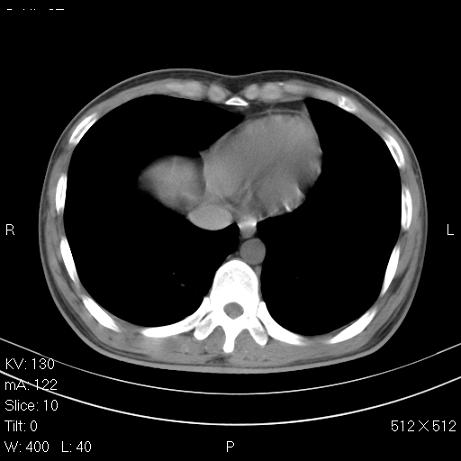

治疗后2周复查,请讨论

结合以前的ct片,还是考虑肺挫伤,吸收多了。

支持:创伤性湿肺。现肺挫裂伤(出血 积气)大部分吸收。建议继续治疗!

结合以前的ct片,支持创伤性湿肺。现大部分吸收。

支持:创伤性湿肺、肺挫裂伤。现肺挫裂伤(出血、渗出、液气腔)大部分吸收。建议继续治疗!

支持:创伤性湿肺、肺挫裂伤。现肺挫裂伤(出血、渗出、液气腔)大部分吸收.

结合老片支持创伤性湿肺、肺挫裂伤。

经治疗后病灶明显吸收,考虑创伤性湿肺、肺挫裂伤

应该为多发性外伤性肺囊肿.

我认为还是值得商榷,排除一下是否为肺动静脉畸形,复查后再看